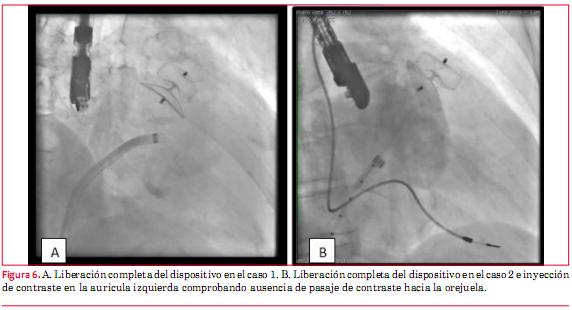

Se seleccionó para ambos casos un dispositivo Amplatzer Cardiac Plug® de 24 mm en función de los diámetros del lóbulo y disco del dispositivo de acuerdo a las medidas obtenidas de cuello y boca. Se utilizó una vaina de 13 Fr tranvenosa cuyo extremo distal se ubicó en el cuello del AAI como instrumento para avanzar el dispositivo de cierre, con especial precaución para prevenir la embolia aérea. Posteriormente, se avanzó el dispositivo hacia el extremo distal de la vaina, liberando primero el lóbulo y luego el disco. Se aseguró que estos se ubicaran en una posición perpendicular con respecto al eje largo del AAI. Se comprobó además la completa expansión y el correcto anclaje del dispositivo (figuras 5 y 6).

En ambos casos se otorgó el alta a las 24 horas indicándose antiagregación plaquetaria, con aspirina durante seis meses y clopidogrel durante un mes. Se realizó seguimiento clínico y ecocardiográfico durante dos años en el caso 1 y por un año en el caso 2, no constatándose eventos clínicos adversos, descartándose en especial la ausencia de manifestaciones cardioembólicas.